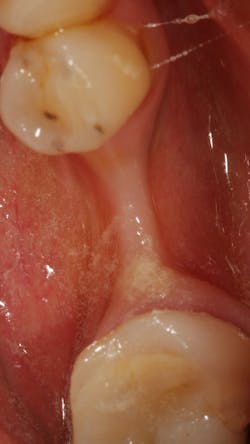

• Rebuild defects around adjacent teeth after extracting teeth due to periodontal disease (figures 5a–5c)